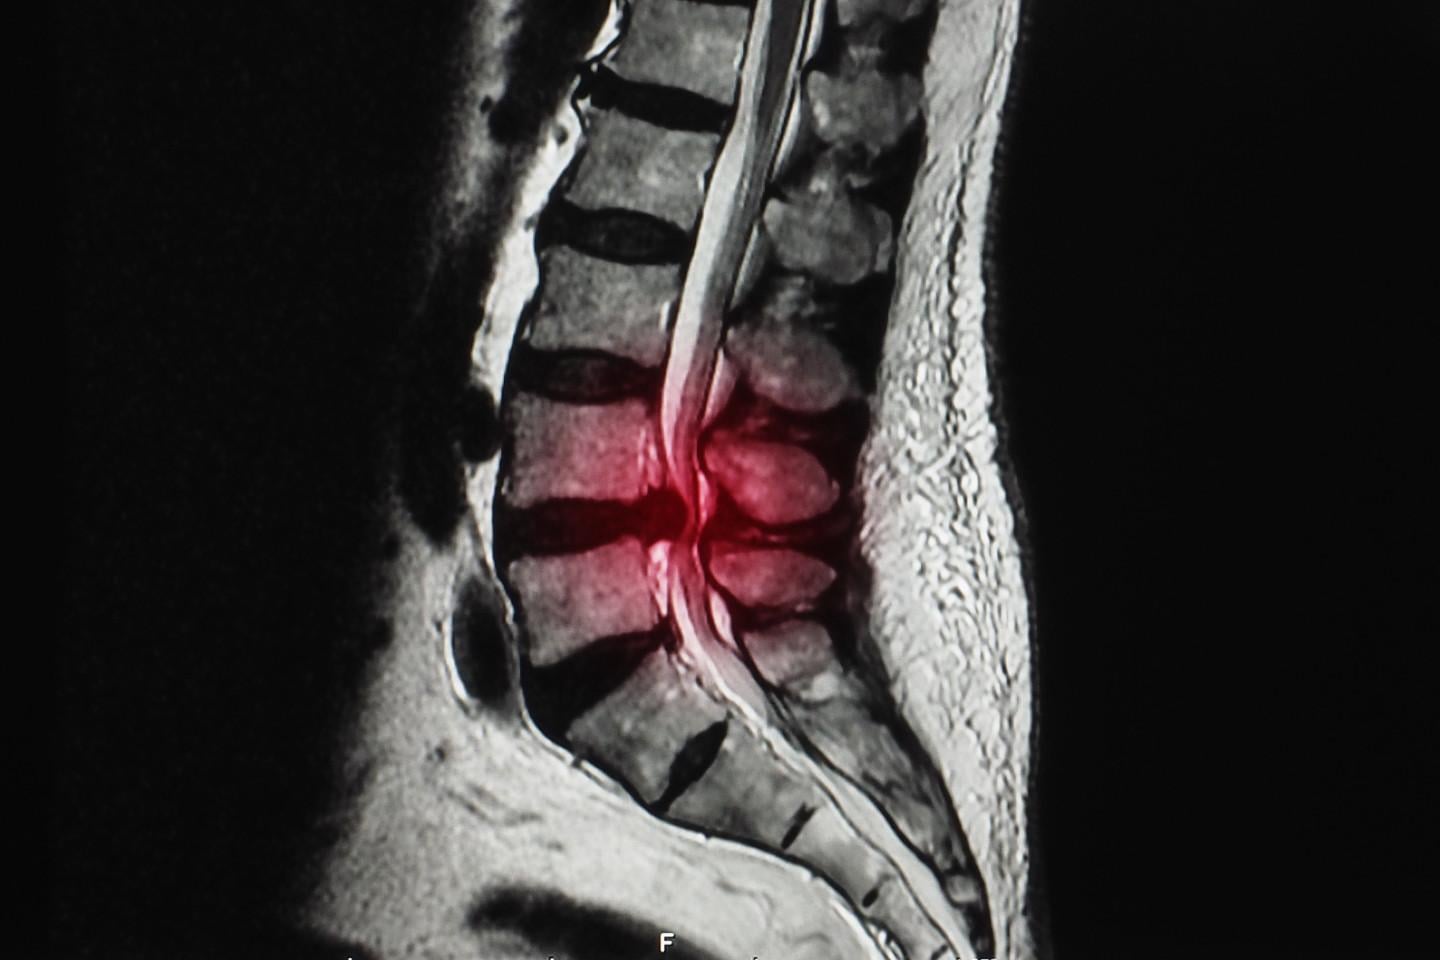

亞洲大學附屬醫院骨科主治醫師林琮凱表示,經安排檢查X光後,影像顯示有退化性脊椎側彎及脊椎滑脫症狀,之後利用磁力共振檢查,也確認有椎孔狹窄合併神經根壓迫情形,揪出真正造成下肢疼痛、麻木、針刺感覺的元兇。

磁力共振檢查助找出下肢疼痛麻木元兇。